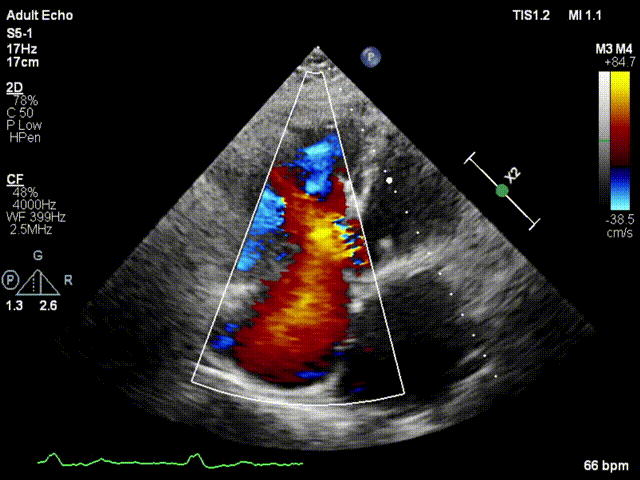

手术在患者全麻状态下进行,采用经右侧颈静脉作为入路,将装载有人工瓣膜的输送器缓慢推送至右心房;并在经食道超声和DSA的引导下小心调整输送器角度,将输送器送入右心室;逐步释放瓣膜锚定装置和盘片,调整瓣膜位置后,锚定瓣膜完成植入。术后右房压明显下降,从术前的25/10(16) mmHg降至术后即刻的12/7(10) mmHg,术后超声提示人工三尖瓣同轴性良好,固定牢固,无反流及瓣周漏手术室即刻拔除气管插管。

术后超声1

术后超声2

术后超声3